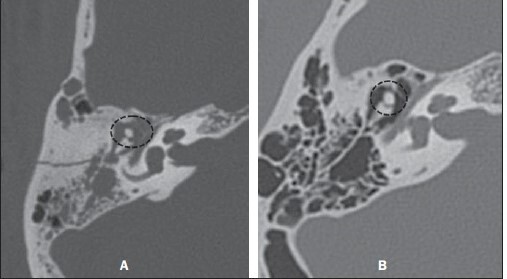

19

Q

Qual o tipo de fratura observada abaixo?

A

LUXAÇÃO INCUDOMALEOLAR (como uma bola de sorvete deslocada da casquinha. Não é a mais comum. A mais comum seria a incudoestapediana, observada na imagem abaixo).